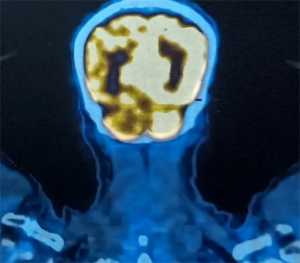

CASE LÂM SÀNG: ĐIỀU TRỊ MIỄN DỊCH BỆNH NHÂN UNG THƯ HẮC TỐ DI CĂN HẠCH, PHỔI TẠI TRUNG TÂM Y HỌC HẠT NHÂN VÀ UNG BƯỚU, BỆNH VIỆN BẠCH MAI. GS.TS Mai Trọng Khoa, BSNT. Mai Thị Quỳnh, PGS.TS Phạm Cẩm Phương, TS. Phạm Văn Thái, TS. Nguyễn Thanh...